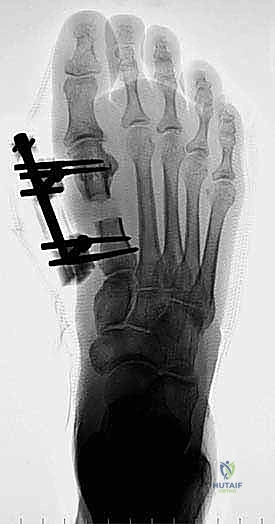

جراحة إطالة مشط القدم الأول: الحل الجذري والنهائي مع أ.د. محمد هطيف

تُعد جراحة إطالة مشط القدم الأول من العمليات الدقيقة التي تتطلب تخطيطاً هندسياً حيوياً معقداً. الهدف هو زيادة طول العظم بالمقدار الدقيق الذي يعيد توزيع الوزن بشكل طبيعي دون إحداث شد زائد على الأوتار والأعصاب.

الخطوة الخامسة: التثبيت الداخلي القوي (Internal Fixation)

لضمان التئام العظم في وضعه الجديد والطويل، يجب تثبيته بقوة شديدة. يستخدم الدكتور هطيف أحدث الشرائح المعدنية التيتانيوم ذات الزاوية الثابتة (Locking Plates) والمسامير الدقيقة. هذا التثبيت القوي يمنع أي حركة بين العظام ويسمح ببدء العلاج الطبيعي في وقت مبكر.

بعد التأكد من الطول المثالي واستقرار التثبيت باستخدام الأشعة السينية في غرفة العمليات، يتم غسل الجرح بمضادات حيوية وإغلاق طبقات الأنسجة والجلد بخياطة تجميلية دقيقة لتقليل الندبات قدر الإمكان. يتم وضع ضمادة ضاغطة وداعمة للقدم.